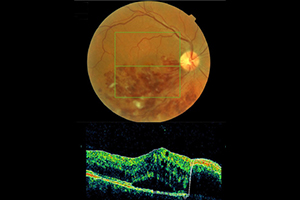

Beispiel: Venöser Gefäßverschluss

58-jähriger Patient mit plötzlicher Sehminderung seit 6 Wochen auf 0,1 (10%). Nach 3-maliger Anti-VEGF Therapie Rückgang des Ödems und Besserung auf 0,63

Fundusfotographie

Mit einer Funduskamera, einer speziell für die Netzhautfotografie entwickelte Kamera, werden Veränderungen an der Netzhaut zur Sicherheit fotografisch untersucht und dokumentiert. Wegen der hohen Auflösung und je nach Aufnahmewinkel ermöglicht sie präzise Aufnahmen insbesondere des Sehnerven, der Netzhaut, der Blutgefäße und der Aderhaut. Spezielle Filter liefern dabei Informationen, die bei der einfachen augenärztlichen Untersuchung verborgen bleiben. Der Vergleich von Aufnahmen, die zu unterschiedlichen Zeitpunkten aufgenommen wurden, ermöglicht eine genaue Beobachtung von Krankheitsverläufen. Bei Veränderungen kann somit zeitnah eine entsprechende Therapie oder Therapieanpassung vorgenommen werden.

Bei weitgestellter Pupille (Achtung: keine Fahrtauglichkeit für mindestens 4 Stunden nach der Untersuchung!) werden mit Hilfe eines Auslösers nacheinander mehrere Bilder von der Netzhaut angefertigt. Die Untersuchung ist berührungsfrei und dauert nur wenige Minuten.

Was kann ich von der fotografischen Dokumentation erwarten?

Durch die Farbfotografien können wir sehr viel genauer das aktuelle Stadium der Erkrankung mit den Ergebnissen der vorangegangenen und künftiger Untersuchungen vergleichen. Selbst kleine Veränderungen lassen sich zuverlässig beurteilen. Am Computerbildschirm können wir Ihnen die Befunde im Anschluss an die Untersuchung nachvollziehbar erläutern und – wenn es erforderlich ist – gemeinsam mit Ihnen das weitere therapeutische Vorgehen besprechen.